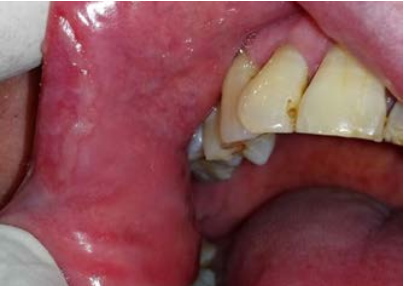

Al examen clínico se pueden observar múltiples lesiones en la cavidad bucal ubicadas en mucosa labial inferior, zona retrocomisural, cara ventral de lengua y tercio posterior de paladar blando y amígdalas, placas blancas de aspecto opalino compatible con pápulas sifilíticas de tres semanas de evolución, dolorosas, con adenopatías submaxilares y occipitales bilaterales positivas e indoloras (Figuras 1 a 4). El diagnóstico presuntivo fue de sífilis secundaria.